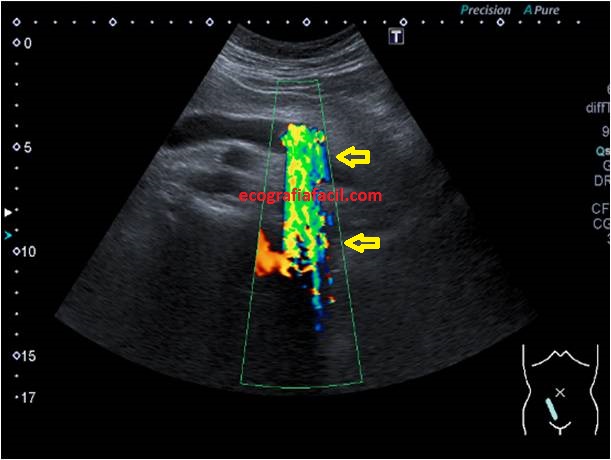

7

La imagen 7 te demuestra una imagen como de flujo cuando colocamos en la zona de la sombra acústica, es un artefacto ecográfico provocado por una lectura anómala o incoherente provocado por el conflicto que le supone al equipo la densidad cálcica de la litiasis. Es un artefacto característico de la litiasis, se llama aliasing y podemos usarlo para esclarecer este tipo de patologías. Te recomiendo usarlo en tu próximo hallazgo de este tipo.